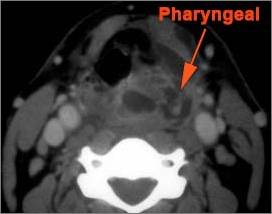

Oropharynx and Nasopharynx

There is excessive enhancement or thickening of the mucosa or hypertrophy of the pharyngeal, palatine or lingual tonsillar tissue or the lymphoid tissue along the glossotonsillar sulci and posterior pharyngeal wall. [Yes/No]

There is edema or abscess within the fat of the adjacent parapharyngeal and retropharyngeal space. [Yes/No]